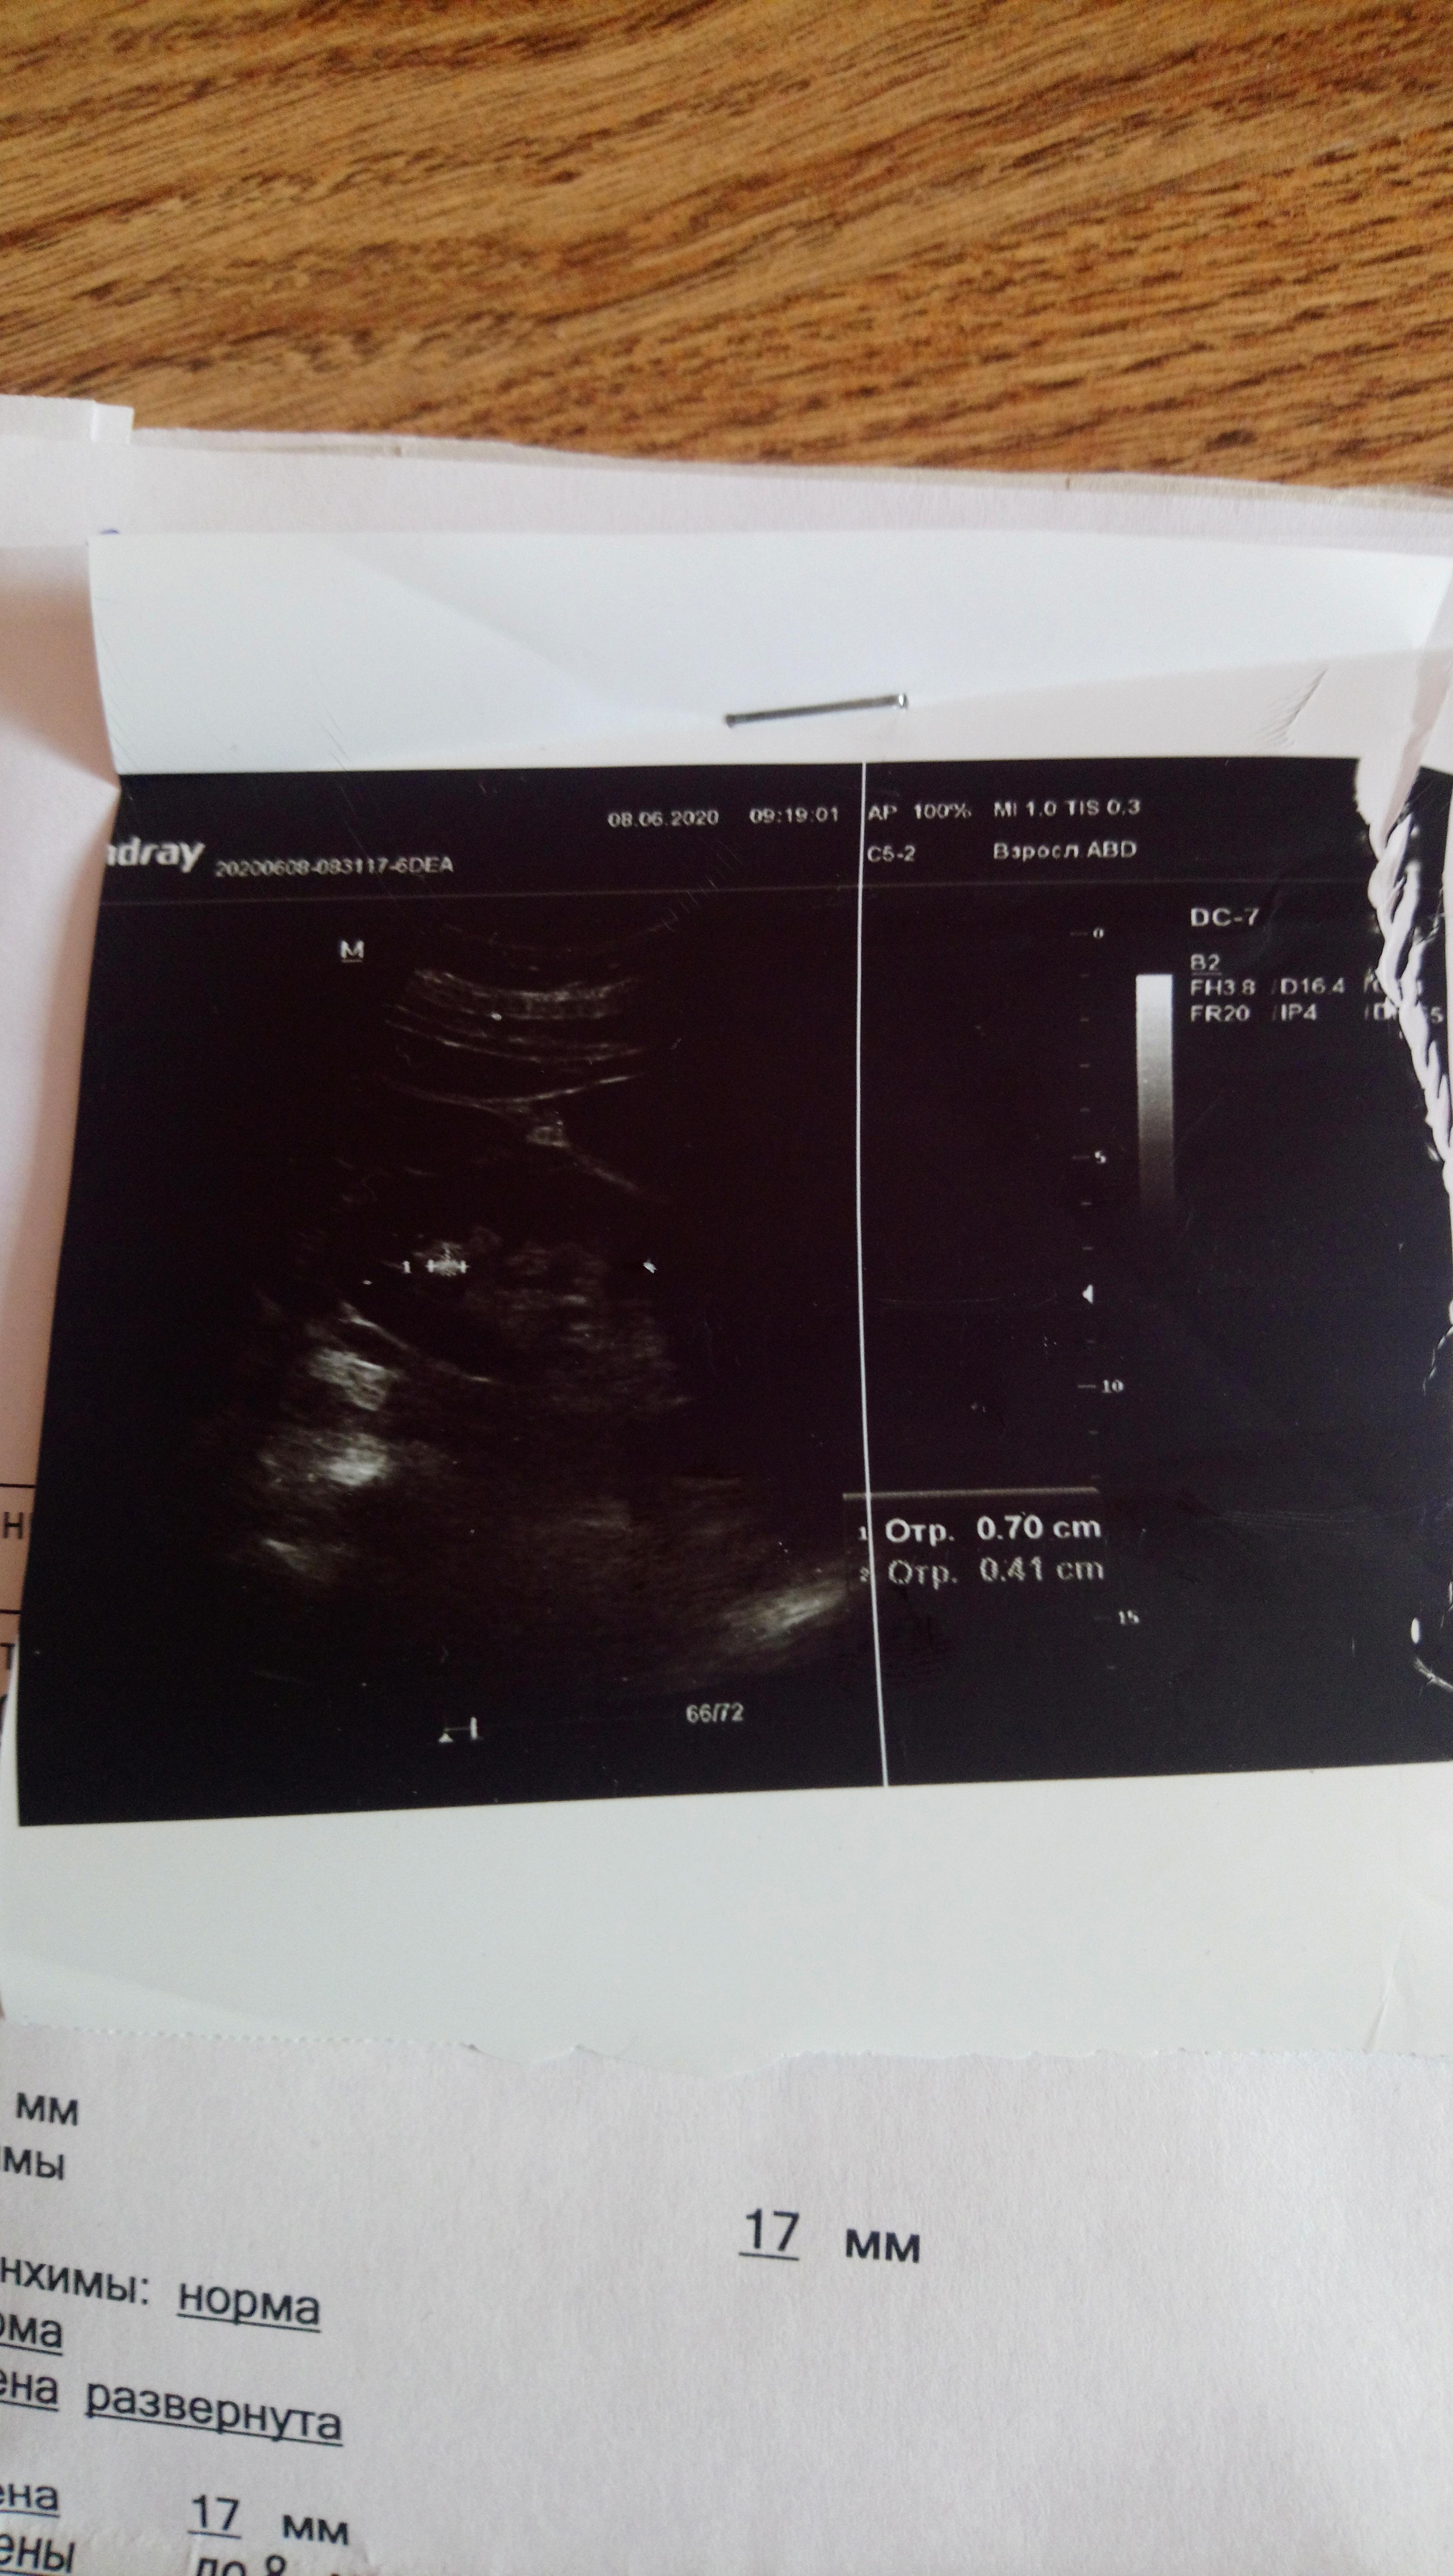

Здравствуйте! Учитывая наличие в моче уратов, можно предпологать , что и конкремент уратный, но необязательно. Целесообразно сделать МСКТ с контрастом - почек и мочеточников ,с 3х мерной реконструкцией. По плотности конкремента можно будет с большей вероятностью предполагать его состав. При конкрементах из солей мочевой кислоты бычно применяют цитратные смеси. При подозрении. по плотности оксалатного характера конкремента, можно рекомендовать комплекс Оксалит. Обсудите эти нюансы с Вашим врачом. Удачи!